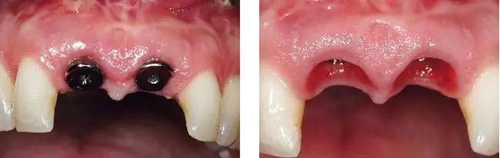

圖12、種植體植入后2個(gè)月取出愈合帽,可見牙齦外形和齦乳頭維持得相當(dāng)好。

圖13、安放全瓷基臺(tái)。

圖14、最終修復(fù)體就位,冠頸部較窄。沒有任何牙齦和牙齦乳頭的退縮。